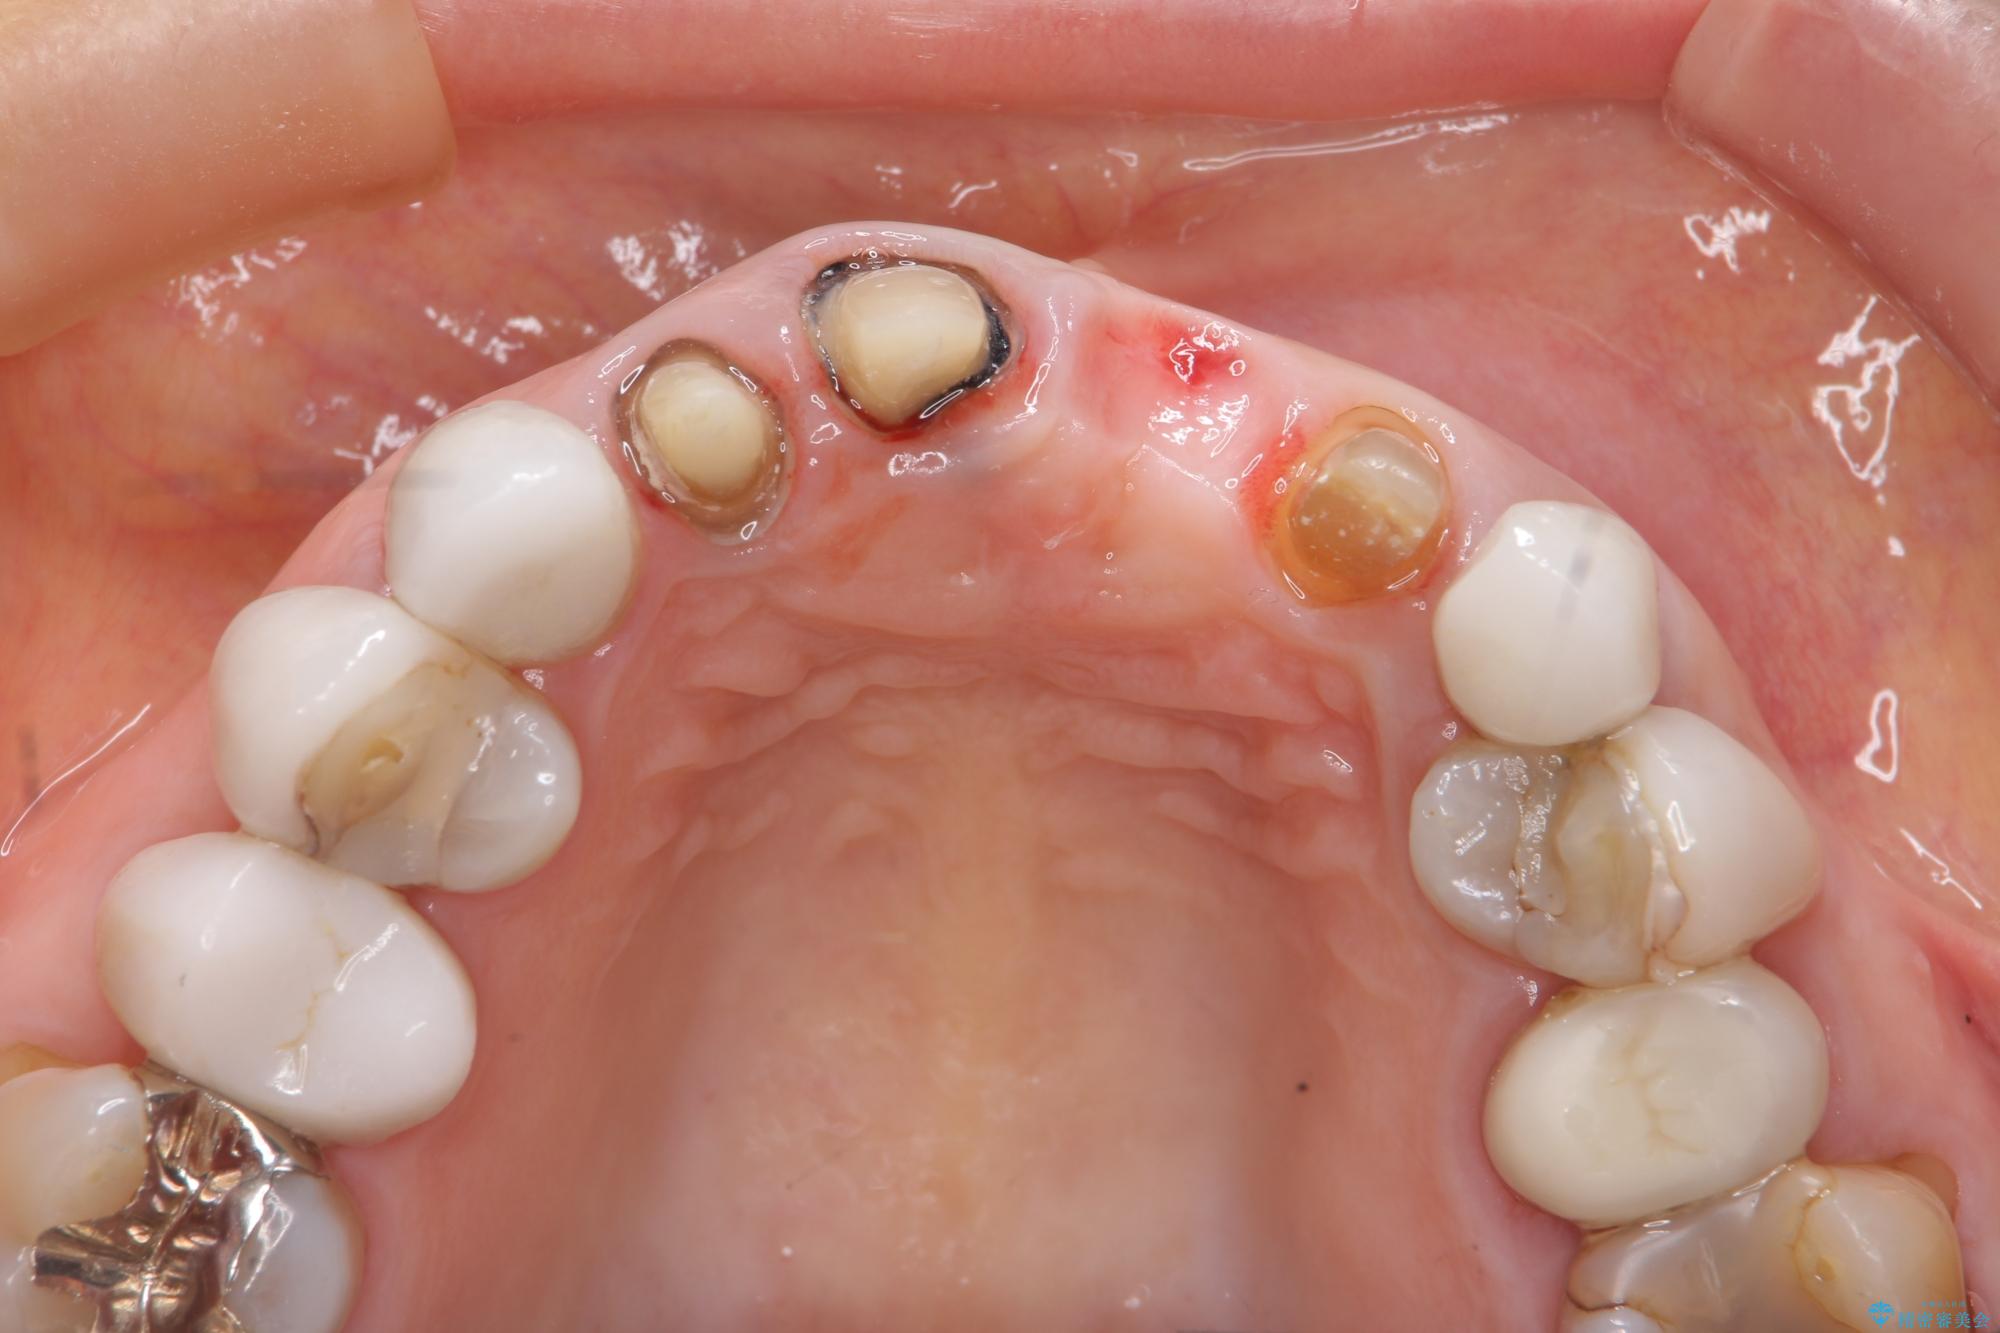

[ セラミック治療 ] 歯ぐきの際の黒ずみを改善したい

- 歯ぐきとセラミックの間の黒ずみが目立つので、きれいに治してほしい。と希望され来院されました。

歯ぐきの位置が変化しクラウン下の歯が見えるようになってしまったことで、審美障害が生じている状態です。

クラウンマージンの再設定を行うことで、黒ずんだ部分を再度覆い、審美障害を改善します。

歯ぐきの位置の経年的な変化は、誰にでも起きうる変化です。

強いブラッシングや電動歯ブラシの当て過ぎなども原因の一因となることがあります。